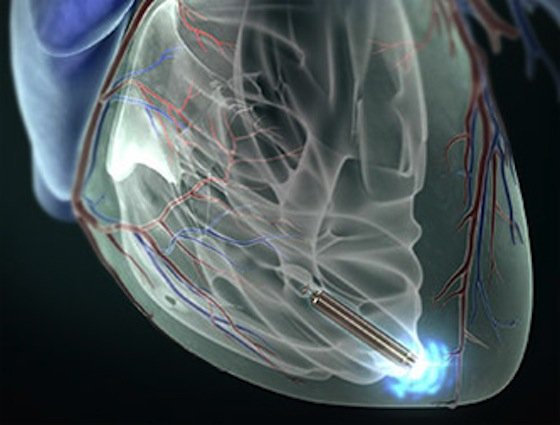

Der Herzschrittmacher Nanostim wird ohne Operation über ein Katheder direkt ins Herz eingeführt. Ohne Verkabelung stimuliert er den Herzmuskel, die Batterie hält 13 Jahre lang.

Foto: St. Jude Medical

Vorsichtig schiebt der Kardiologe den Katheter in die Beinvene. An seiner Spitze ist ein kaum zigarettengroßes Gerät befestigt, der weltweit erste Schrittmacher, der direkt im Herzen platziert wird.

Konzentriert verfolgt der Operateur auf seinem Monitor den Weg des Katheters durch den Körper des Patienten. In der rechten Herzkammer angekommen löst er Nanostim Leadless Cardiac Pacemaker, wie der Schrittmacher heißt, vom Katheter und zieht diesen zurück. Das Gerät registriert die Herztätigkeit und gibt elektrische Impulse ab, wenn der Rhythmus nicht mehr stimmt. Bis zu 13 Jahre lang hält die Batterie. Dann wird das Gerät auf dem gleichen Weg entnommen und durch ein frisches ersetzt. Die minimal-invasive Operation dauert im Durchschnitt nur knapp 30 Minuten.

Der Herzschrittmacher Nanostim wird ohne Operation über ein Katheder direkt ins Herz eingeführt. Ohne Verkabelung stimuliert er den Herzmuskel, die Batterie hält 13 Jahre lang.

Quelle: St. Jude Medical